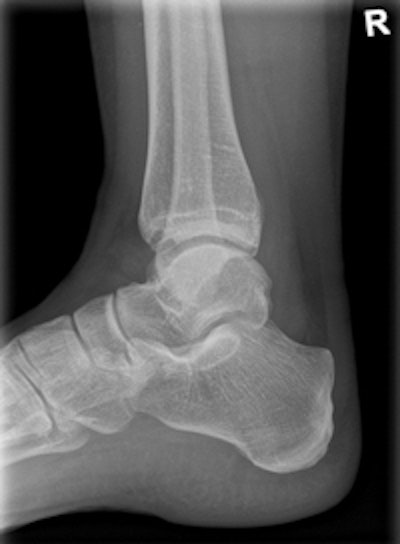

Clinical image of an x-ray examination of the ankle joint. Copyright: Radiology Department, University Hospital Erlangen, Germany. Image courtesy of Siemens.The machine can record static, dynamic, and real-time 3D sequences, and the full range of its potential applications is still to be explored. But there are clinical applications in which it already appears to have advantages over CT, notably in investigations of upper limb fractures in obese patients and weight-bearing lower-limb bone examinations of diabetics, he added.